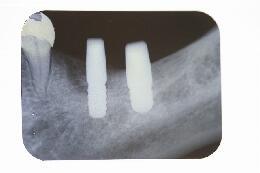

埋入手術当日

インプラントの埋入手術当日のエックス線写真です。手前の骨の密度が上がらないので少し 埋入位置を後方へ設定